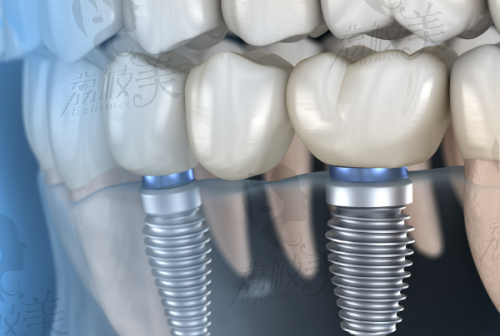

牙齿缺失不仅影响饮食和发音,还会给我们的容貌大打折扣。如今越来越多的人选择种植牙来重塑自信笑容。其中,韩系种植牙凭借稳定性能、亲民价格和平衡的性价比在众多植体品牌中突出重围,成为不少人种牙“入门级”的优选。漳州呀哚口腔引进了包含登腾、奥齿泰等品牌在内的韩系种植系统,借助数字化导航设备,配合经验多的口腔医生团队,让整个种牙过程安心、效率高。当前,漳州呀哚口腔韩系种植牙·轻松上牙舞“技”!优价4680元起种出笑口常开的活动正在火热进行中,满足不同咬合状态、预算需求的市民,让幸福“齿”在必行。

韩系种植牙指的是原产于韩国的种植体品牌,常见有登腾DENTIUM、奥齿泰Osstem等。它们以良好的骨结合性和经济实惠的价格受到大众青睐。对中老年人或预算有限的青年用户来说,是非常理想的选择。

数字化导板和CT三维成像系统配合精细评估,有效避免神经损伤、位置偏移等问题;让植体稳固扎根,并实现自然、美观的牙冠修复。

2. 韩国奥齿泰种植体 4980元起:使用内六角接口、粗螺纹设计,适应性更广,更适用于牙槽骨骨量限制的患者。

3. 数字化微创植入:在数字导板辅助下,严谨打孔并植入种植体。过程约30分钟。